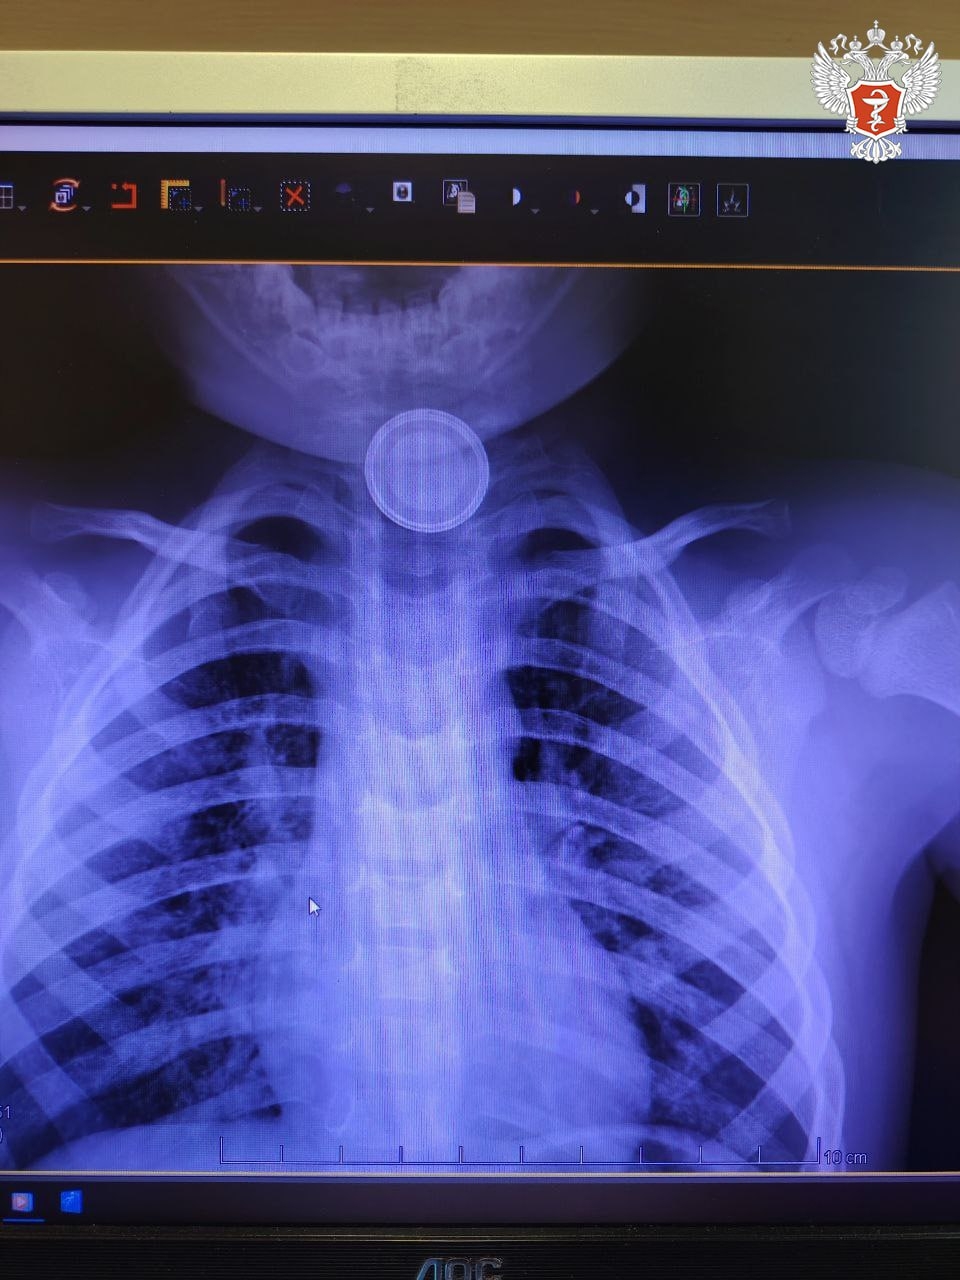

Годовалый ребенок поступил в Нижневартовскую окружную клиническую детскую больницу с затруднённым глотанием и слюнотечением. Врачи выполнили рентген и выявили круглое инородное тело в верхней трети пищевода.

➡ Специалисты приняли решение о проведении экстренной операции и извлекли батарейку, но предмет успел нанести вред здоровью пациента.